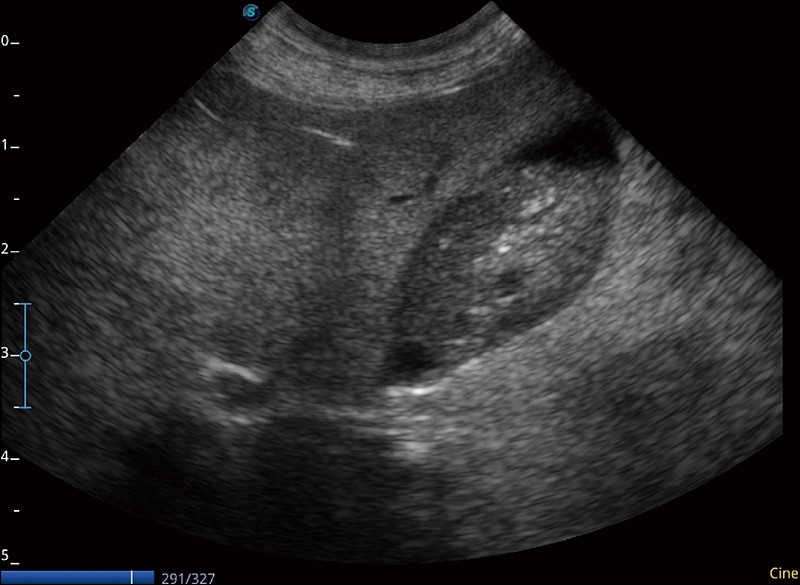

扩展成像

支持线阵和凸阵探头,一键操作即可获得更宽的图像视野